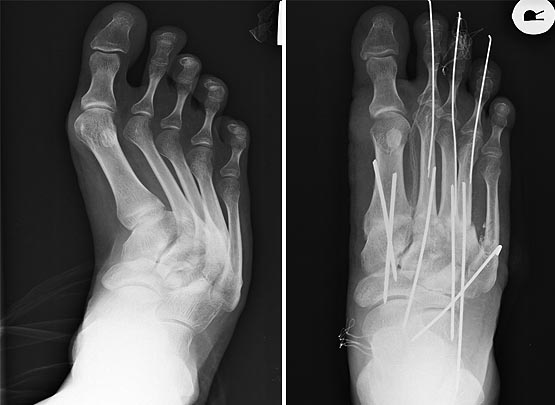

Полностью поддерживаю вопрос господина Бережного и в качестве иллюстрации предлагаю вот такое изображение.

Предварительный план следующий: устранить отклонение 2 и 3 плюсневых костей (проксимальная остеотомия) с фиксацией спицами, медиальный плюснеклиновидный артродез и устранение молоточкообразной деформации 5 пальца (резекция основной фаланги) с трансартикулярной фиксацией.

Глубокоуважаемый Сергей Юрьевич! Сделать как хочет больная (исправить деформацию 5 пальца и устранить бурсит 1 ПФС), на мой взгляд и с большой степенью вероятности означает получить рецидив через 2-3 года. Поэтому думаем выполнить операцию по ниже предложенному плану. Начнем, я думаю, с устранения отклонения 2 и 3 плюсневых костей через доступ во втором межплюсневом пространстве, остеотомия проксимальная и фиксация спицами с одновременным устранением отклонения 2 и 3 пальцев и их фиксацией спицами. Далее переходим на 1 плюсневую. Тут пока вопрос: делать медиальный плюснеклиновидный артродез или клиновидную проксимальную остеотомию, фиксировать винтом и 1 палец трансартикулярно спицей. Сесамовидные снизу, поэтому насчет латерального релиза не уверен. В завершение устранение деформации 5 пальца. Здесь пока склоняемся к резекции основной фаланги.